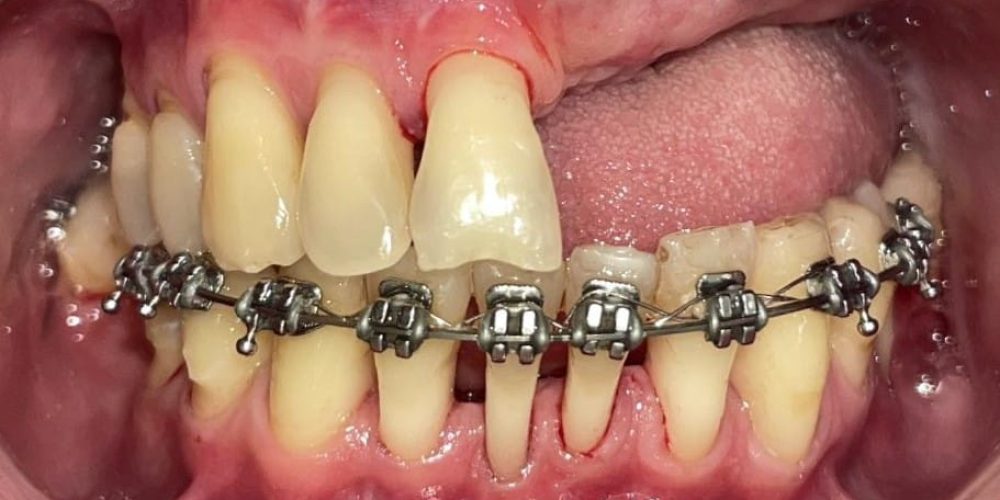

Boală parodontală tratată cu menținerea unor dinți și înlocuirea celor irecuperabili cu implanturi.

Pierderea dinților cu deficit osos considerabil, rezolvat prin tratament multidisciplinar, intervenții chirurgicale de adiție osoasă, implanturi dentare, grefe gingivale, tratament ortodontic si protetic pentru redarea zâmbetului si a funcției masticatorii

Sub anestezie locală, medicul chirurg inserează implantul dentar cu ajutorul unui fiziodispenser de mare precizie. Procedura este rapidă, nedureroasă, iar recuperarea este bine pusă la punct prin protocoale de analgezie. Totodată, analizam si calitatea țesuturilor moi si unde este necesar, realizam si grefe gingivale.